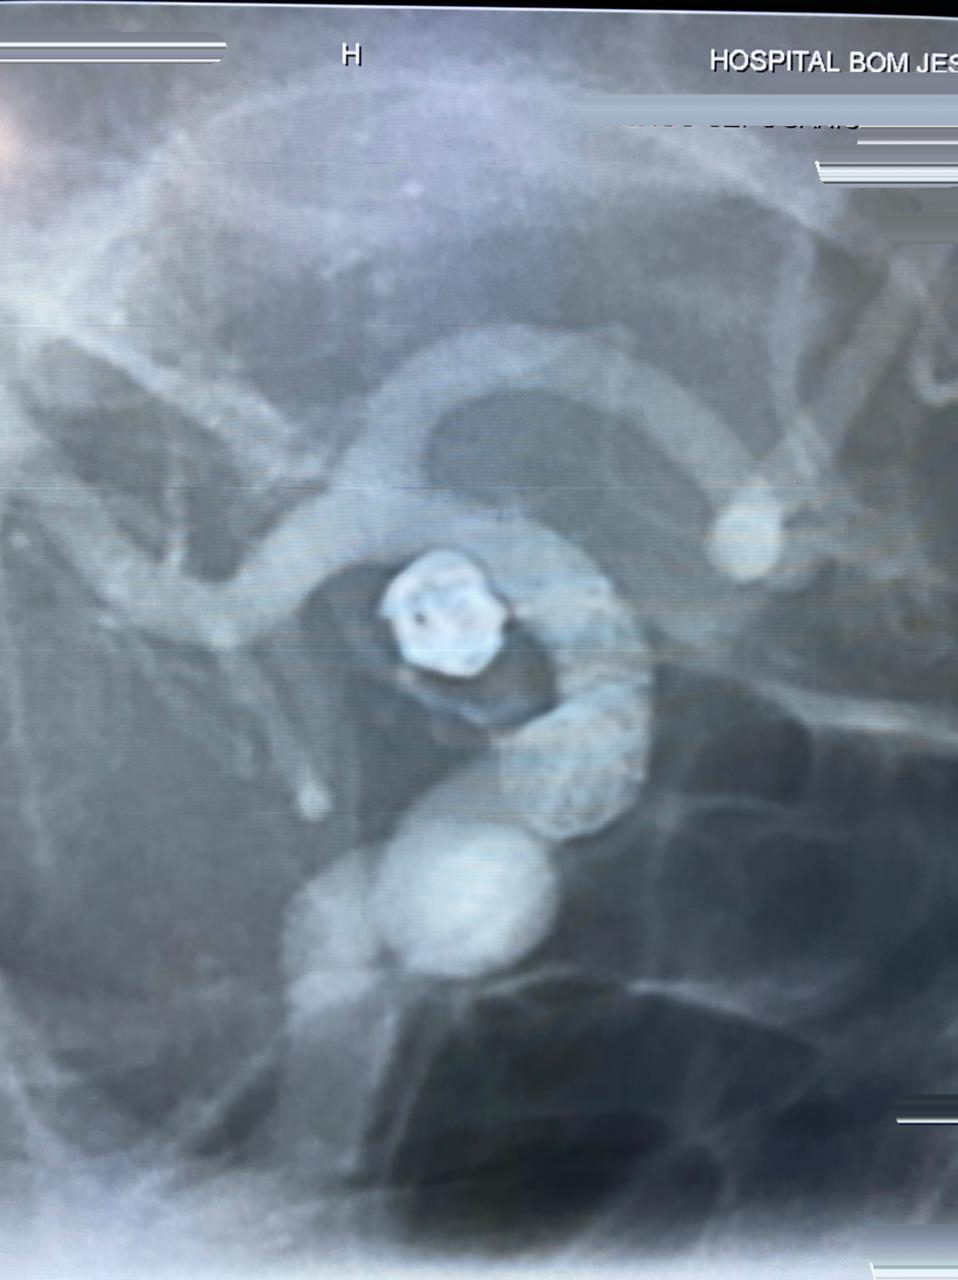

HCorBJ realiza procedimento de Embolização de Aneurisma Cerebral

O procedimento de Embolização de Aneurisma Cerebral é realizado no Setor de Hemodinâmica, sob anestesia geral, com um aparelho de imagem de última geração. O tratamento endovascular, é uma opção minimamente invasiva para as doenças cerebrovasculares.

Dr. Jivago Szpoganicz Sabatini, médico neurologista e neurorradiologista intervencionista que realizou o procedimento destaca, “esse procedimento usa uma tecnologia inovadora, trazendo excelentes resultados, usando o que há de melhor no mundo, em benefício dos pacientes neurológicos.”

“O primeiro caso de Embolização de Aneurisma Cerebral em Ponta Grossa, com stent diversor de fluxo, foi realizado no Hospital do Coração Bom Jesus em dezembro de 2018, o HCorBJ tem estrutura excelente para isso, tanto para realização do método, quanto no atendimento pós- operatório dos pacientes na Unidade de Terapia Intensiva (UTI) e enfermaria, com equipes altamente especializadas”, ressalta Sabatini.

A última intervenção realizada no HCorBJ, contou com a participação do Dr. Gelson Luis Koppe, médico neurorradiologista intervencionista de Curitiba.